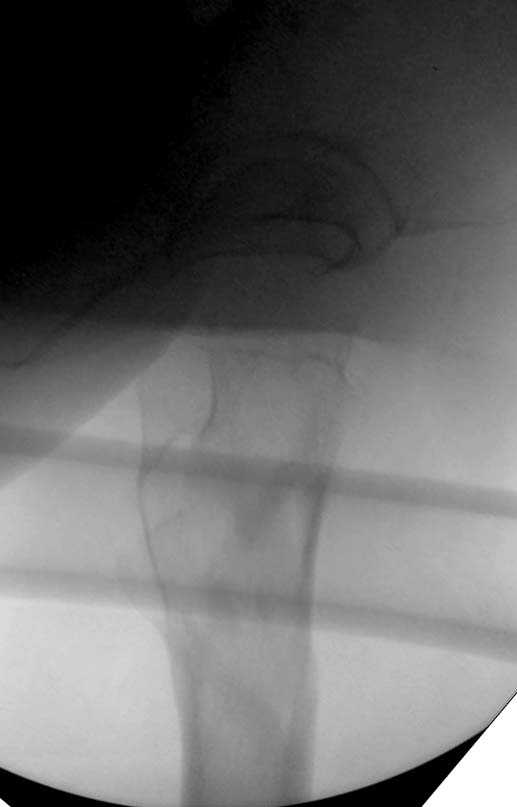

Здесь представлен случай, где в послеоперационном периоде обнаружена техническая ошибка, Gamma 3 установлен с нарушением методики. Больная в 91 лет, прооперирована через день после поступления и выписана через 48 часов.

При первом послеоперационном поликлиническом осмотре больная предъявила жалобы на боли в бедре. В серийных снимках обнаружен продольный перелом верхнего отдела бедра.

Считаем, что техническая ошибка произошла во время установки гвоздя, когда рассверливанию канала не уделили должного внимания. Канал остался узковат, и гвоздь был забит с силой. Полная нагрузка конечности приостановлена на две недели, и боли в конечности изчезли. Больная начала нагрузку и перелом срастается. -- Djoldas Kuldjanov, M.D. Associate Professor Department of Orthopedic Surgery St. Louis University